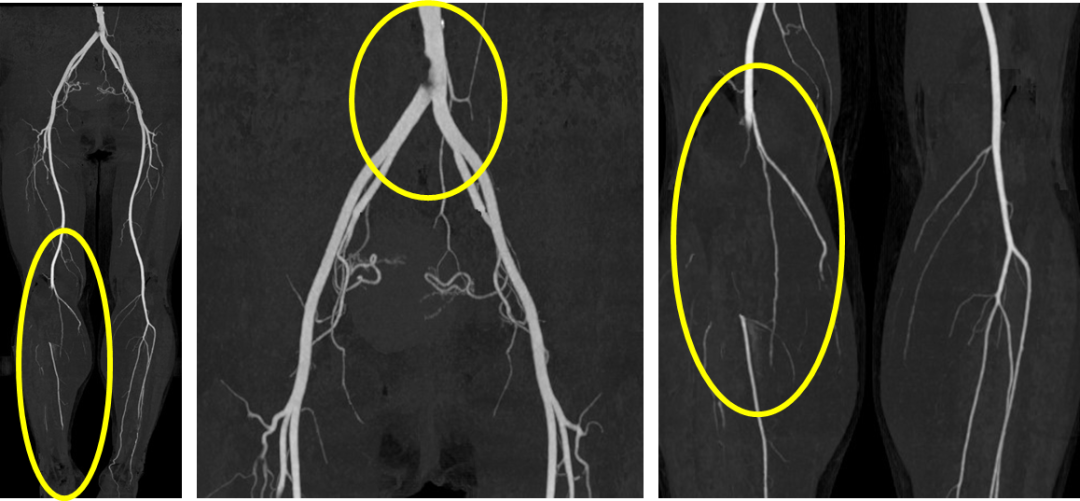

术前CTA

诊疗方案: